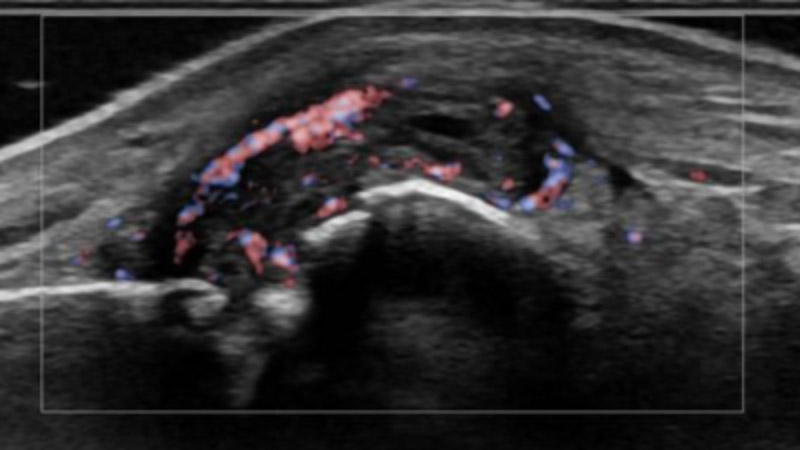

Siêu âm sử dụng sóng âm tần số cao để tạo ra hình ảnh các cơ quan và mô trong cơ thể. Bác sĩ sẽ bôi một lớp gel mỏng lên da, sau đó đặt đầu dò lên vùng cơ thể (tùy bộ phận bị ảnh hưởng). Đầu dò chuyển đổi dòng điện thành sóng âm tần số cao và truyền vào cơ thể. Sóng âm dội lại từ cấu trúc bên trong và trở lại đầu dò. Đầu dò chuyển sóng thành tín hiệu điện. Máy tính sẽ chuyển tín hiệu điện thành hình ảnh, video.

Sóng siêu âm có thể dùng để chẩn đoán các vấn đề về xương khớp: